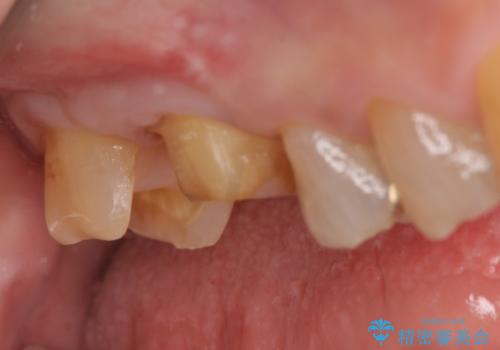

その後歯茎の回復を待ち、オールセラミッククラウンおよびセラミックインレーによる補綴・修復を行いました。

当院のセラミックインレーはemaxという強度と審美性に優れた材料を使用しています。

またプレス方式でインレーを製作しているため、削り出しで製作するCADCAMより優れた適合性も持ち合わせており、虫歯が再発しにくい修復物です。

今回用いたオールセラミッククラウンはジルコニアフレームという白い素材の上にセラミックを盛っているため、審美性が非常に高いのが特徴です。

また、ジルコニアは人工ダイヤモンドの材料にも使われているほど高い強度を持っており、そのためオールセラミッククラウンは審美性だけでなく、奥歯やブリッジの補綴も可能とするクラウンです。